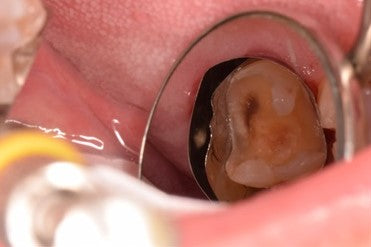

Lingual root Class V caries on #18

Lingual root caries on molars can be hard to access and keep isolated. Before Step 1 Class V subgingival caries on the mesial lingual root of #18 Prepped Step 2... Read More